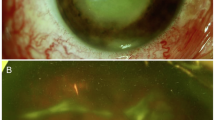

Elevated IOP of over 21 mmHg was defined as ocular hypertension. 46 of 120 eyes (38.3%) had ocular hypertension. The mean IOP in the poor final VA group was 26.3 ± 11.7 mmHg, which was significantly higher than that of the favorable final VA group (16.5 ± 9.9 mmHg; OR, 1.1; 95% CI, 1.0–1.2; p = 0.003). Furthermore, one third (36/118) of the eyes exhibited clear cornea at presentation, whereas 78% (64/82) eyes with corneal edema had a significantly poor final VA (OR, 6.4; 95% CI, 2.3–18.0; p < 0.001). The presence of a hypopyon was identified as a risk factor for poor VA outcomes (OR, 3.9; 95% CI, 1.5–9.9; p = 0.003). The mean height of the hypopyon was 1.8 ± 1.4 mm in 49 of 120 eyes; however, the height of hypopyon did not affect final visual outcomes in this study. Subretinal abscess was identified at presentation by fundoscopic and ocular sonographic examination or during the TPPV. 113 eyes (94.2%) had subretinal abscess, but 73.5% (83/113) of them presented with poor finial VA. Eyes having subretinal abscess had a prognostic factor for poor visual outcomes (OR, 6.9; 95% CI, 1.3–37.6; p = 0.0252).